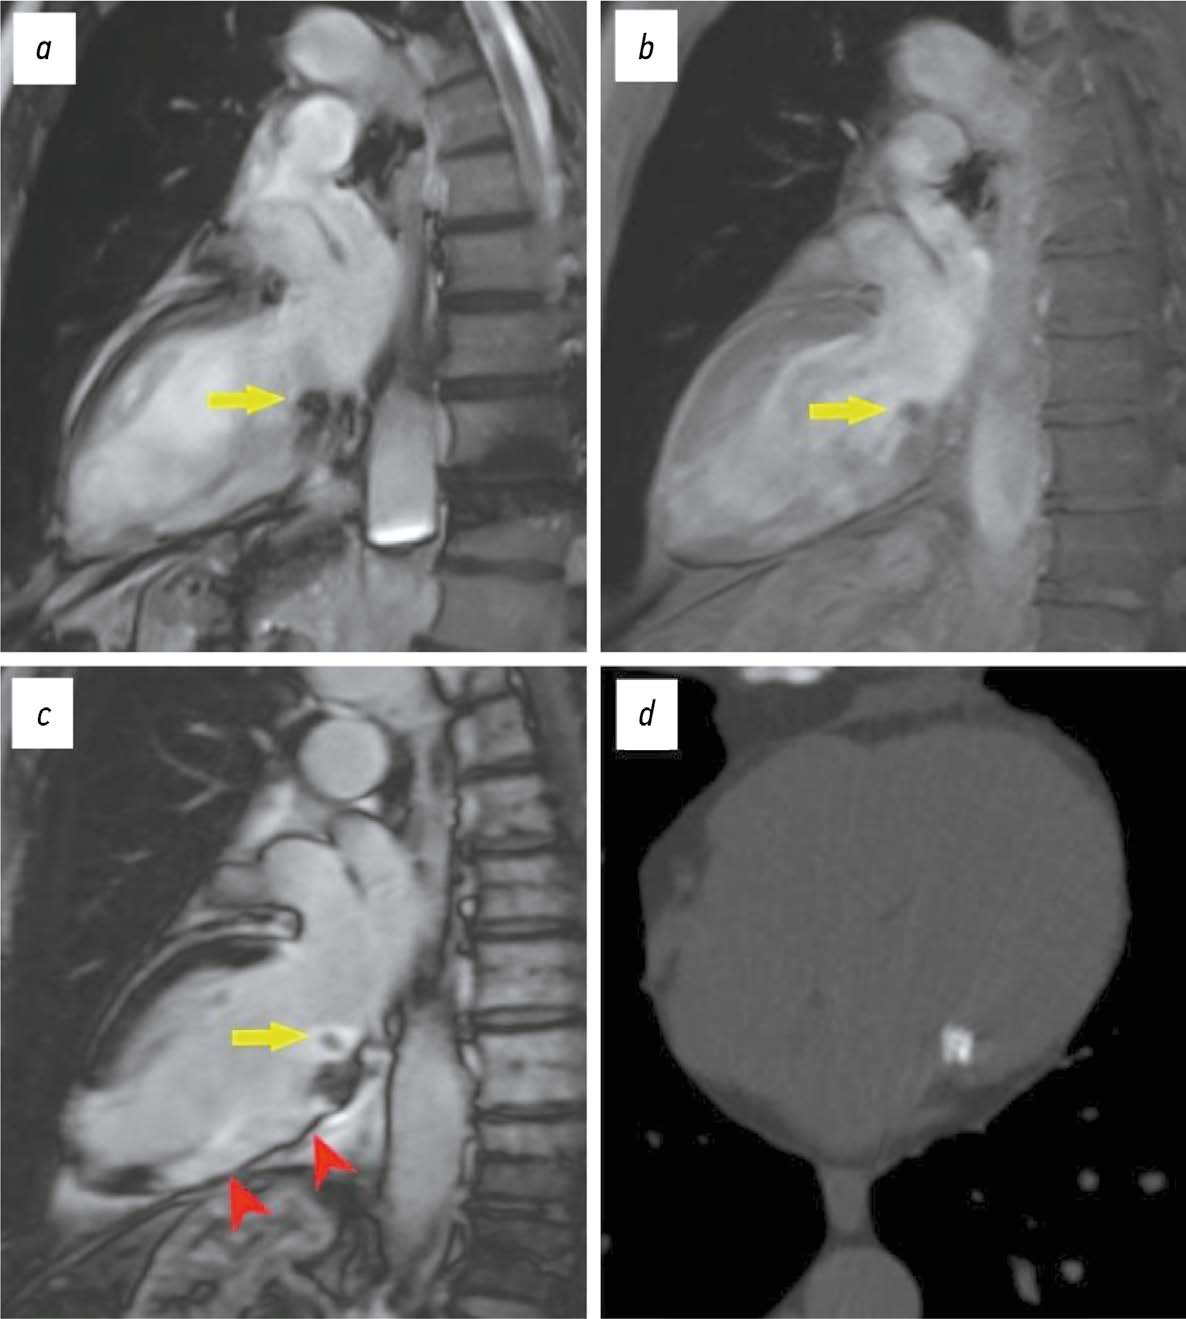

Дифференциальная диагностика интракардиального объёмного образования в области кольца митрального клапана, выявленного при проведении эхокардиографии, может быть непростой задачей. Её решение обычно требует мультимодального подхода. Очень часто природа такого образования связана с подклапанным кальцинозом митрального клапана. Наибольшую трудность в диагностике представляет достаточно редкий его вариант — казеозная форма. На примере представленной серии клинических случаев подчёркивается важность и клиническая значимость компьютерной томографии для выявления и характеристики подклапанного кальциноза кольца митрального клапана при неоднозначных результатах других методов диагностики, в частности эхокардиографии. Данная работа нацелена на повышение информированности специалистов о классических признаках казеозной формы подклапанного кальциноза кольца митрального клапана при визуализации в различных модальностях. Особое внимание уделяется построению дифференциально-диагностического ряда, выделению характеристик, позволяющих отличить подклапанный кальциноз кольца митрального клапана от других патологических состояний в данной локализации. Осведомлённость врачей о существовании такого рода изменений в области митрального клапана необходима для прогнозирования возможных осложнений, связанных с ней, и планирования тактики лечения, что поможет в некоторых случаях избежать неоправданных хирургических вмешательств.